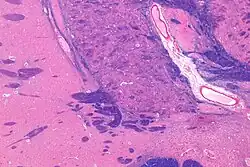

NBM in relation to the globus pallidus and putamen - very low magnification. -

Micrograph of cholinergic neurons in the nucleus basalis of a rhesus monkey; Bar = 50 microns (0.05 millimeters).